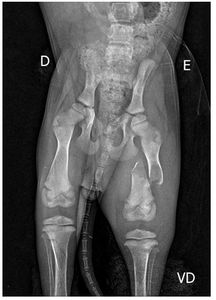

Kiara sofreu um acidente em 05/09 onde acabou fraturando o FÊMUR da perna esquerda e teve uma fissura na perna direita.

o motivo da urgência neste caso é para que a fratura não cicatrize de forma errada, deixando sequelas ou perda da movimentação na perna, além das dores.

as imagens comprovam a necessidade e urgência do caso, contamos com sua colaboração independente do valor, tudo que conseguirmos será bem vindo e ajudará no tratamento dessa pequena que faz parte das nossas vidas.